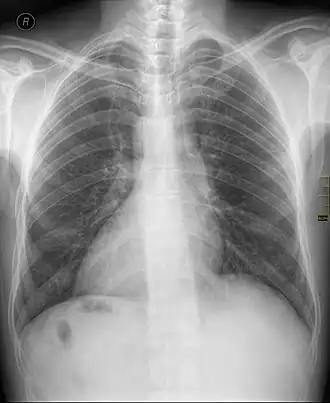

![]() Декстрокардия в рамках situs inversus на рентгенограмме органов грудной клетки. | |

Декстрокардия (от лат. dexter «правый» + др.-греч. καρδία «сердце») — аномалия развития (дистопия[1]), при которой большая часть сердца расположена в грудной клетке вправо от средней линии тела симметрично нормальному положению[2][3][4]. Данное состояние сопровождается «зеркальным» расположением всех кровеносных сосудов, исходящих и входящих в сердце.

Обычно сочетается с зеркальным расположением всех непарных внутренних органов — транспозиция органов. Впервые декстрокардию описал Марко Аурелио Северино в 1643 году.